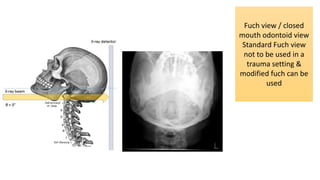

Fuch view / closed

mouth odontoid view

Standard Fuch view

not to be used in a

trauma setting &

modified fuch can be

used